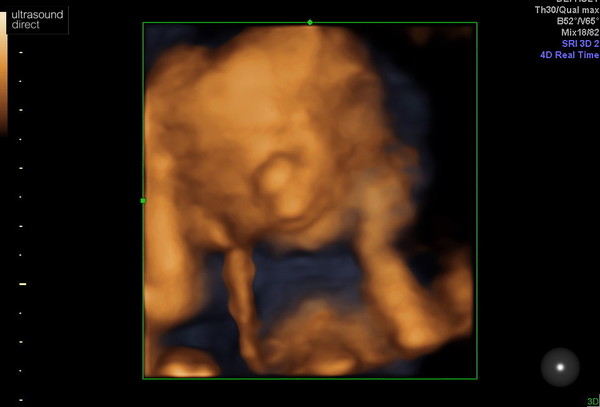

It will. Be so good to see my little man. I had a wee private one again.

And it was the cutest ever he's holding his face and you can see his smile and his nose.